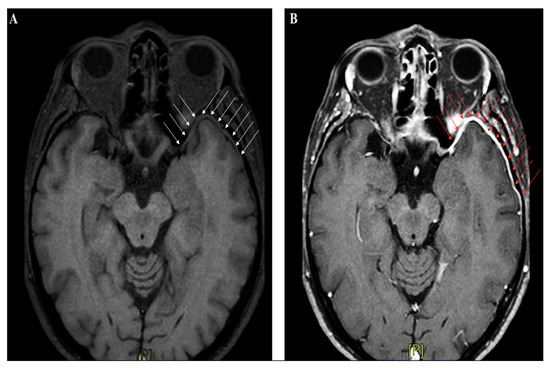

4.4.3. The Role of Neuroimaging in Meningitis

Neuroimaging studies are not crucial for meningitis diagnosis, apart from their role in identifying patients at risk for brain herniation, who should not undergo lumbar puncture. In the early phase, abnormal findings are seldom detected by CT scan; in the Dutch cohort study on community-acquired meningitis, CT was performed on admission in 71% of subjects, and was unremarkable in almost 66% of them [17]. Contrast-CT might identify meningeal enhancement in a minor proportion of cases later on in the disease course. Magnetic resonance imaging (MRI) is not immediately required in uncomplicated meningitides, although gadolinium-enhanced MRI (Gd-MRI) can clearly document the meningeal involvement (Figure 3A–B).

Figure 3.

Brain magnetic resonance imaging (MRI) (axial section, T1-weighted images) performed in a patient with recurrent headache and diplopia, and a history of remote head trauma; a definite thickening of the meningeal lining over the left anterior temporal lobe (white arrow panel A), with following contrast enhancement (red arrow panel B), can be clearly identified.

However, Gd-MRI is crucial for detection of harmful complications such as cerebral ischemia, sinus thrombosis, brain abscess, hydrocephalus, and cerebral edema. Therefore, it should be promptly performed in patients with new-onset focal neurological deficits and seizures, or other signs of clinical deterioration [38,39]. In subjects presenting with TBI, neuroimaging studies are mandatory to detect skull fractures, intracranial bleeding, cerebral edema, and diffuse axonal injury. Brain imaging also play a pivotal role in localizing CSF fistulas, even when no CSF leak is clinically evident (because of meningocele, herniation, bone fragments, or blood clots temporarily obstructing the dural tear) [10]. The early identification of CSF fistulas is strategic to plan therapeutic approaches and estimate the risk of developing post-traumatic meningitis. With this aim, several advanced techniques have been applied, such as high-resolution CT (HRCT), which uses 1–2 mm sections in both the coronal and axial planes to obtain detailed images of the bone structures, or MRI cisternography, a non-invasive technique where T2-weighted images with fat suppression and image reversal allow to highlight CSF and brain parenchyma, despite poor bone definition [10]. However, the current radiological gold standard for identification of the exact site of CSF leak implies the intrathecal injection of a detectable dye, such as fluoresceine (used off-label) or radiopaque contrast followed by CT scanning (so-called CT cisternography), or even (less common) a radioactive substance, used in radionuclide cisternograms [11]. Despite their good sensitivity, these techniques have serious potential complications, including aseptic meningitis due to intrathecal injections of chemical compounds.